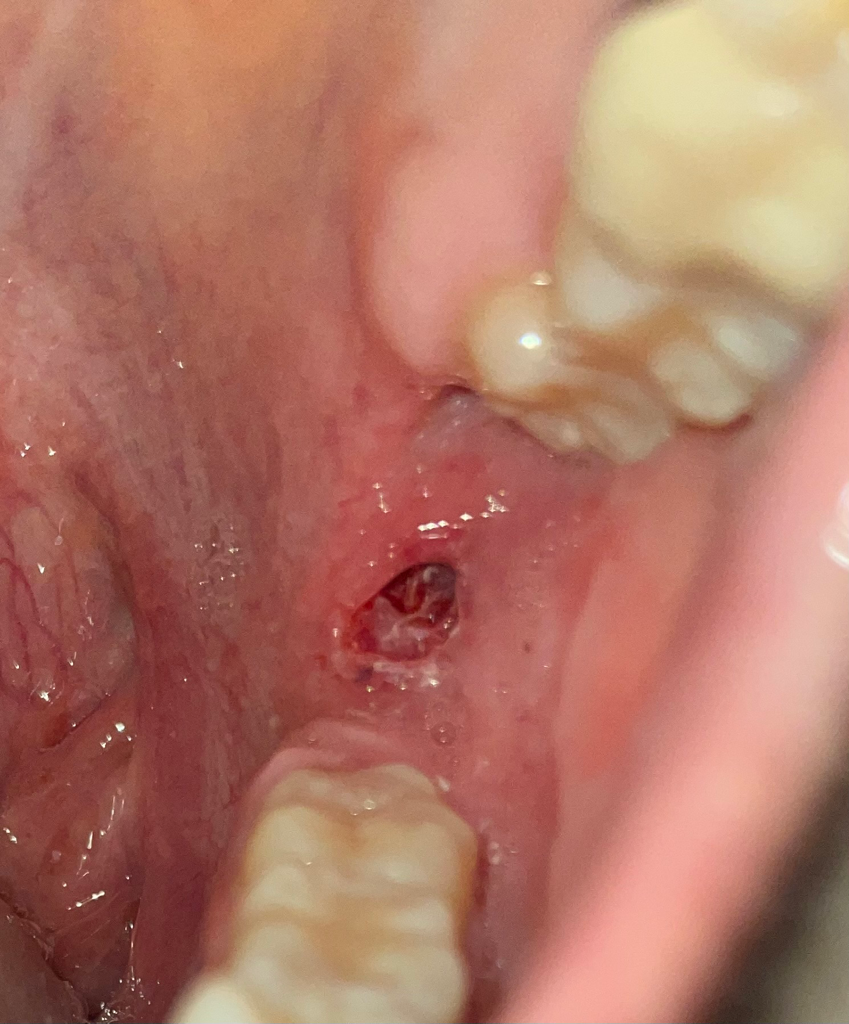

양치하다가 칫솔이 잇몸을 뚫어서 피가나고 구멍나는데 어떻게해야하죠?

양치하다가 친구가 팔로세게쳐서 어금니 뒤 잇몸을 찔렀는데 그대로 구멍이났어요.. 좀 깊게 난거같고 피도나는데 그대로 둬야하나요? 약을 발라야하는지 .. 연고를 발라야하는지ㅠㅜㅜㅜ 진통소염제는 먹었어요 제발 급해요ㅠ 구멍이 얼마나났는지 모르겠는데 1센치는 되는거같아요